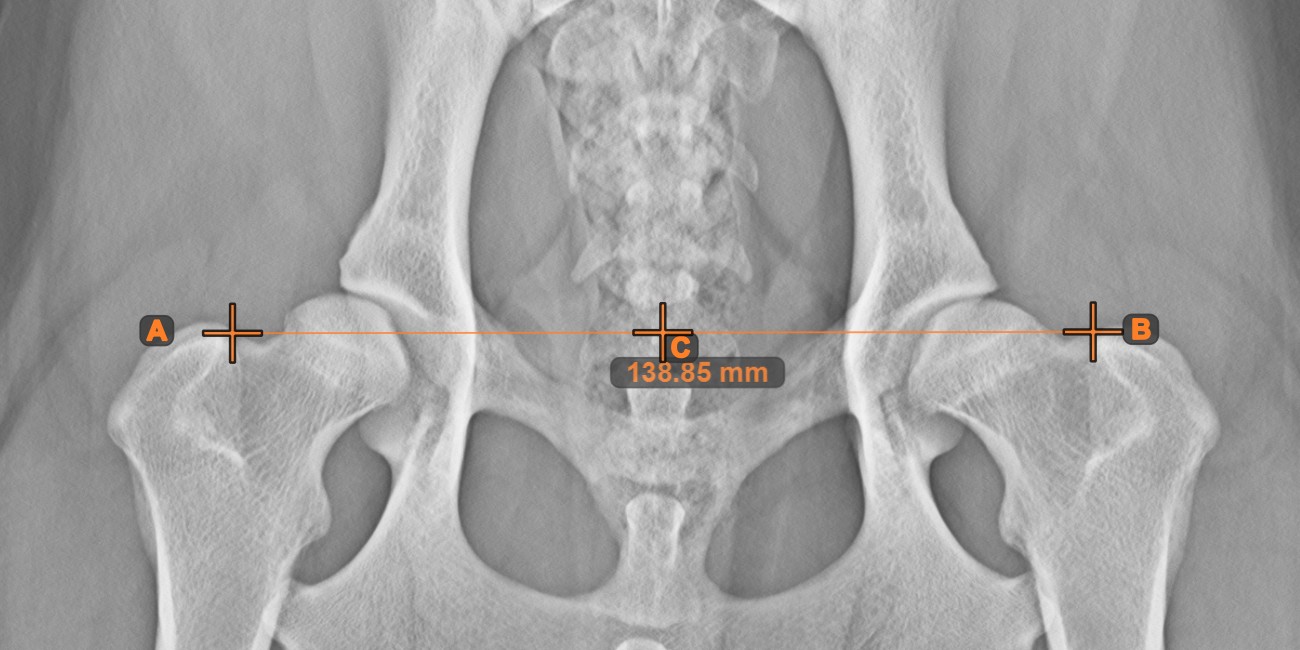

Center Point of Line¶

Identify and mark the center point of a new or existing line measurement on the scene by using the Center Point of Line tool.

Select the tool from the left toolbar and assign it to one of the available mouse buttons. Place the start and end points on the scene, select them from already existing points on the image, or select an already drawn line from the scene. The center point of the line will be automatically calculated and placed on the scene. The center point of each line will always be marked with the letter C.